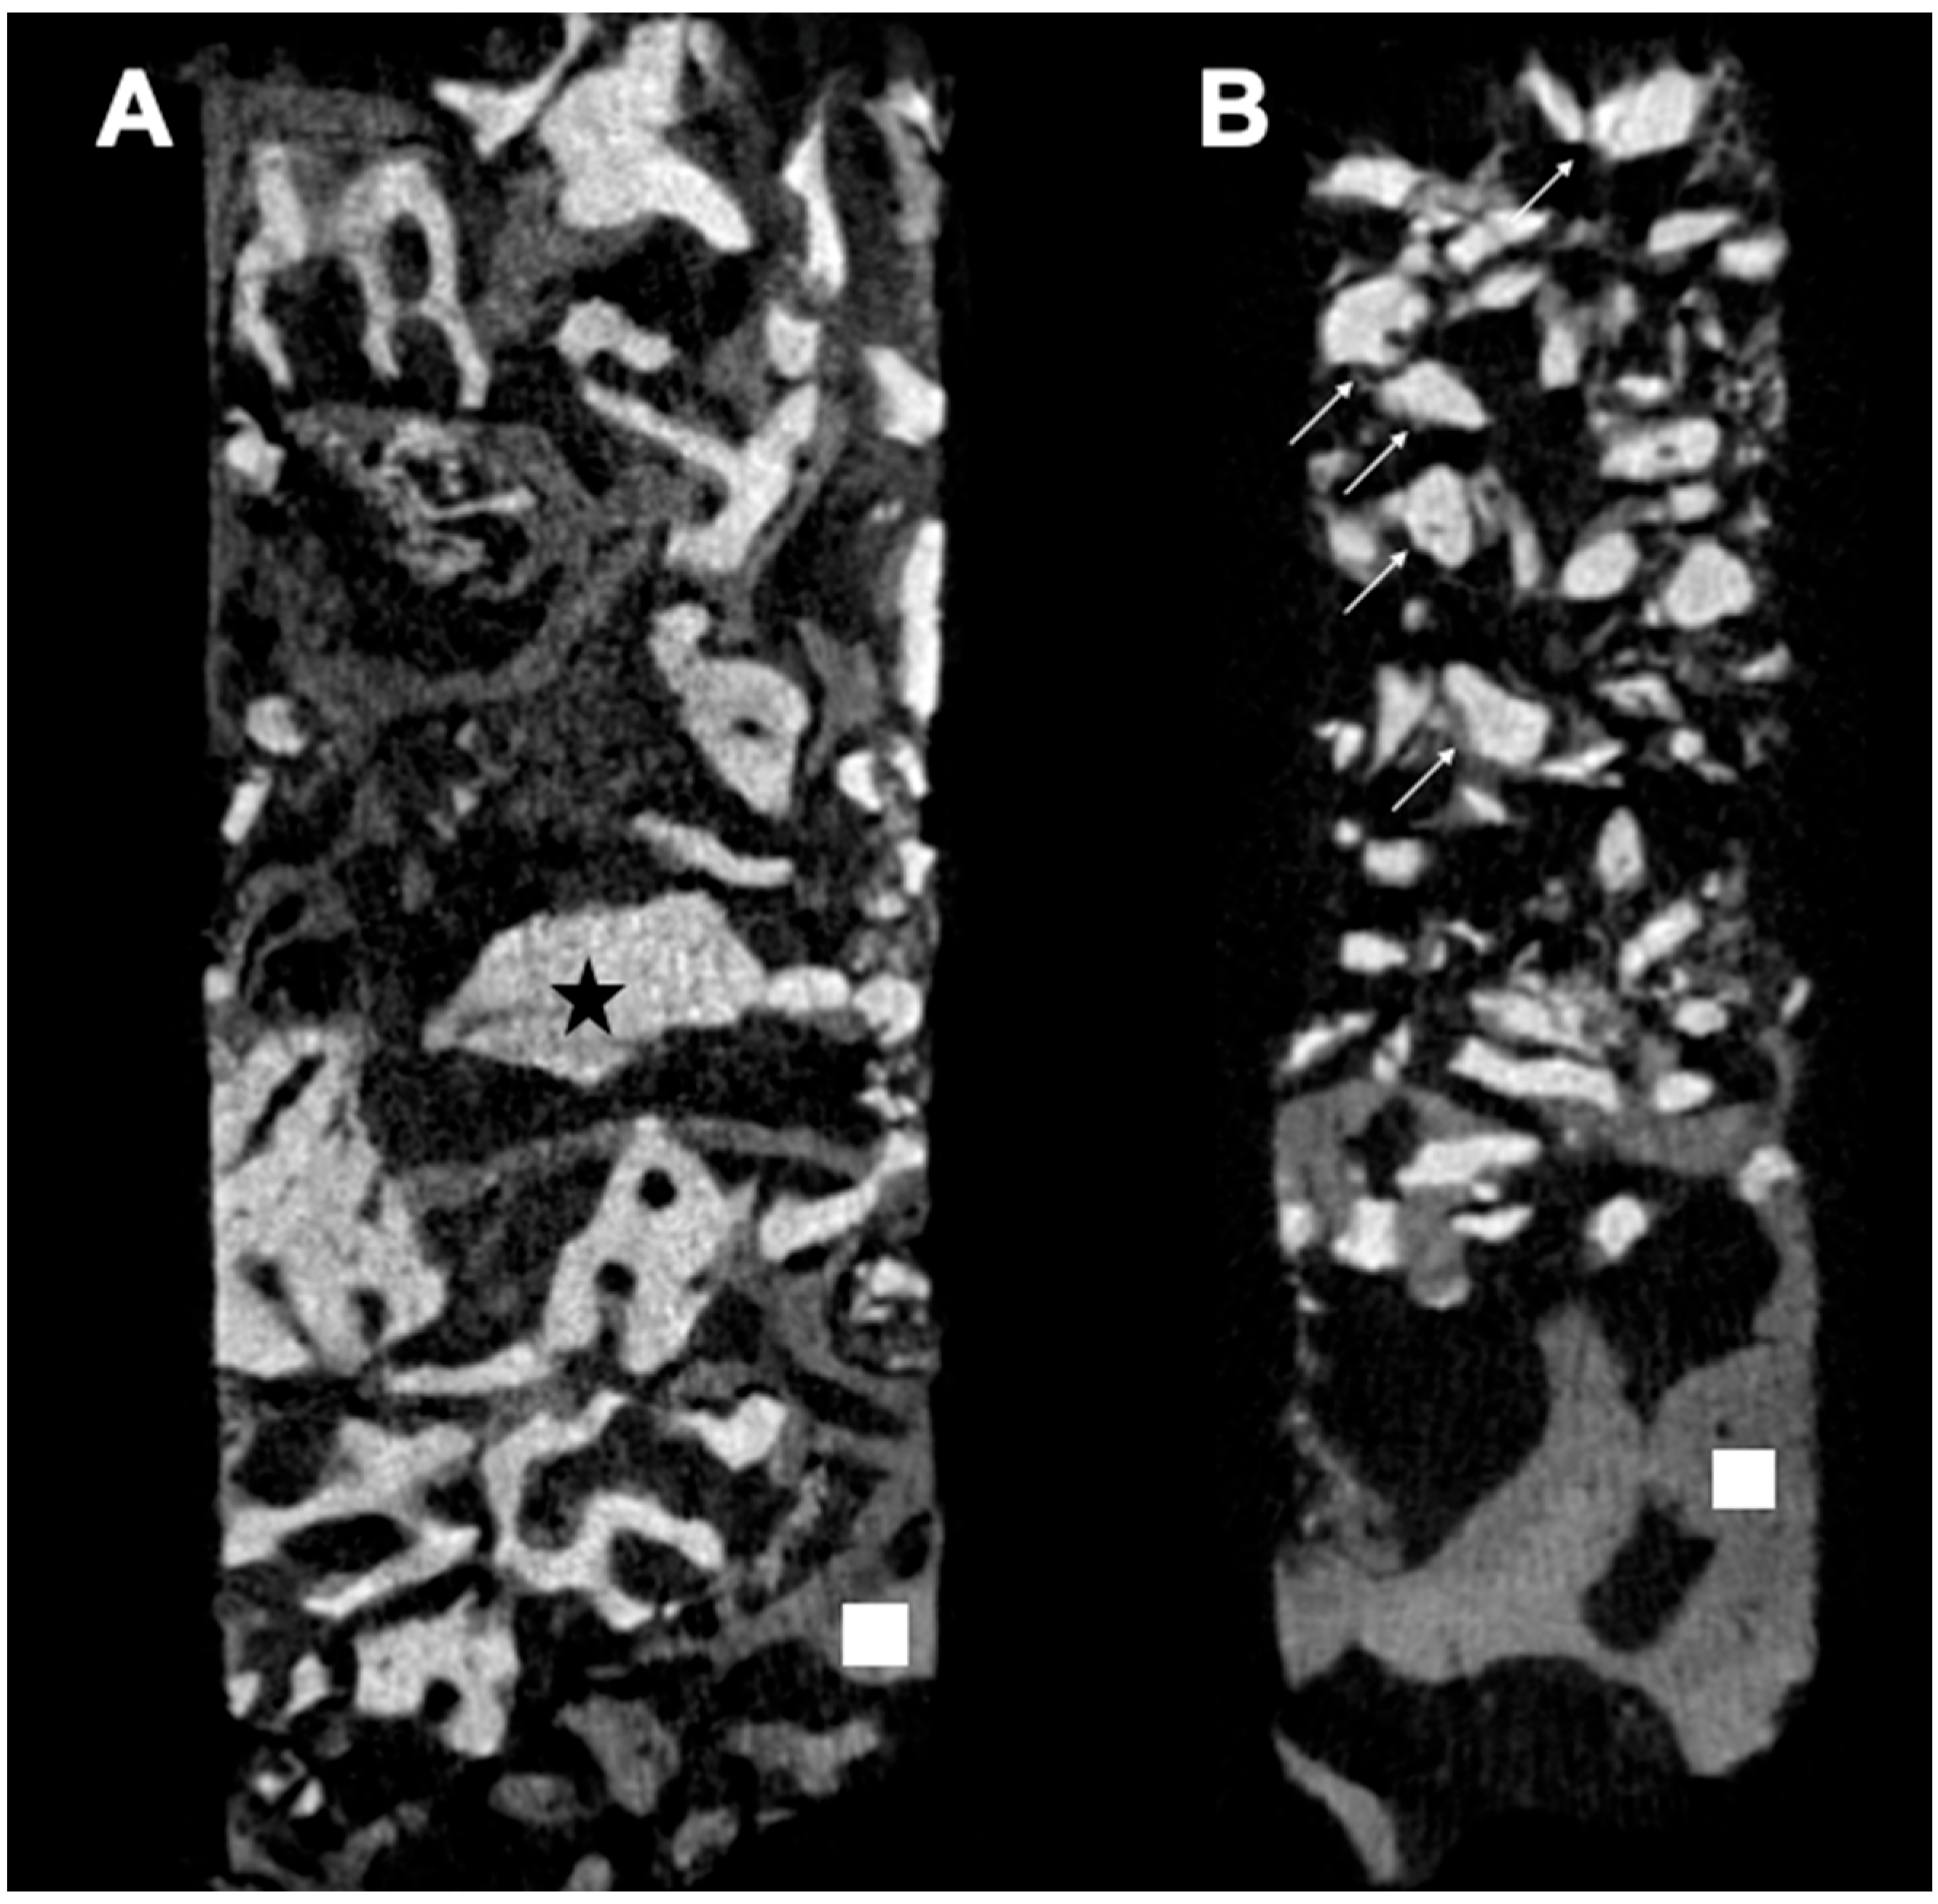

3.3. Micro-CT Analysis

- Pereira, R.D.S.; Menezes, J.D.; Bonardi, J.P.; Griza, G.L.; Okamoto, R.; Hochuli-Vieira, E. Comparative Study of Volumetric Changes and Trabecular Microarchitecture in Human Maxillary Sinus Bone Augmentation with Bioactive Glass and Autogenous Bone Graft: A Prospective and Randomized Assessment. Int. J. Oral Maxillofac. Surg. 2018, 47, 665–671. [Google Scholar] [CrossRef]